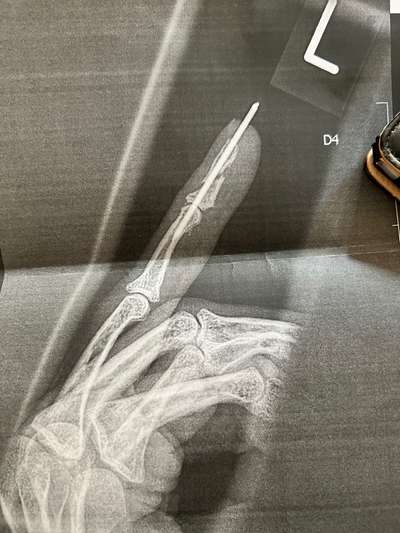

Sieht nach kompliziert und OP aus…. Bei mir hat Titan- Nagel gereicht.

Oh, da wünsche ich auch das alles hoffentlich wieder heil ist🙂. Ja, meiner ist richtig krumm geblieben, trotz Drähten , lange Zeit Ruhigstellung. Es war eine Luxation mit 2 -Facher Fraktur 🤭.